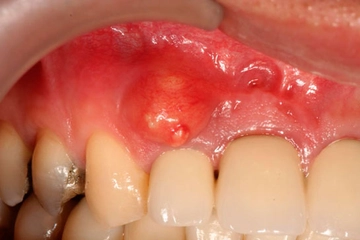

Kök Kalmasının SonuçlarıDiş çekiminden sonra kök kalması, bazı olumsuz sonuçlara yol açabilir:

Kök kaldığında tedavi kompleksite seviyesi; kökün boyutu, konumu, enfeksyon varlığı ve hastanın genel sağlık durumuna göre değişir. Küçük, asemptomatik kökler bazen takip edilebilirken, çoğunlukla cerrahi müdahale gerekir. Bu işlem normal çekimden daha detaylı olup lokal anestezi altında diş eti kesisi ve kemikte küçük bir pencere açılmasını içerebilir.